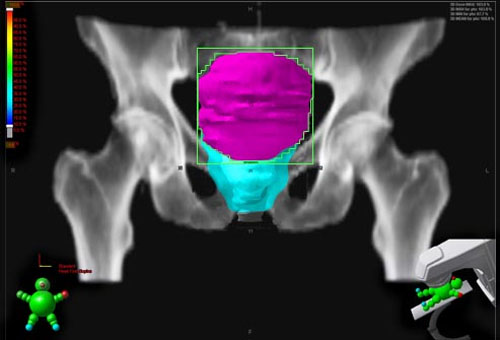

- Xạ trị: Đây là phương pháp điều trị trong đó người ta sử dụng những tia có năng lượng cao để tiêu diệt các tế bào ung thư. Giống như phẫu thuật, xạ trị là phương pháp điều trị tại chỗ do đó chỉ có tác dụng diệt các tế bào ung thư tại vùng chiếu xạ.

Xạ trị là phương pháp điều trị tại chỗ do đó chỉ có tác dụng diệt các tế bào ung thư tại vùng chiếu xạ.

Một số ít bệnh nhân có thể điều trị bằng tia xạ trước khi phẫu thuật với mục đích thu nhỏ thể tích của khối u làm cho việc phẫu thuật sau đó dễ dàng hơn. Còn đa số các bệnh nhân khác điều trị bằng tia xạ được áp dụng sau phẫu thuật để tiêu diệt nốt các tế bào ung thư còn sót lại. Ngoài ra, đối với những bệnh nhân không còn khả năng phẫu thuật thì áp dụng biện pháp xạ trị cũng có cơ hội chữa được bệnh.